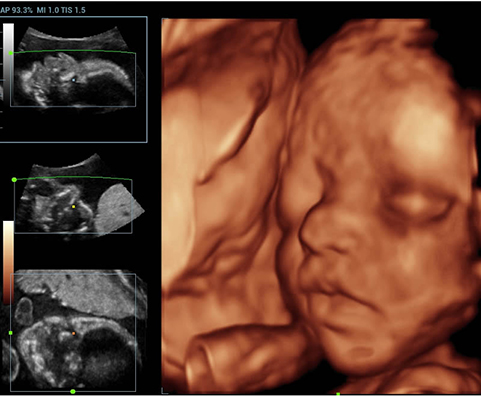

Обеспечивая качество изображения уровня премиум, Resona 7 также повышает клинические возможности исследования при помощи революционной системы V Flow, предназначенной для оценки гемодинамических показателей сосудов; обеспечивает интеллектуальное получение из 3D данных наиболее важных проекций для диагностики ЦНС плода. Сочетая в себе интуитивно понятное сенсорное управление с распознаванием жестов и все важные клинические характеристики, передовая система Resona 7 настоящая новая волна в сфере ультразвуковых инноваций.Благодаря перечисленным выше характеристикам, Resona 7 является доступным решением премиум-класса, которое удовлетворяет высоким требованиям клинической точности и эффективной диагностики в условиях современной перегруженной больничной среды.